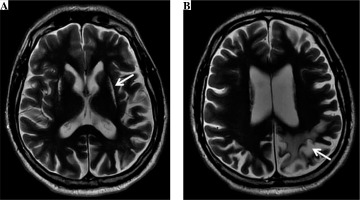

Nine years after the cerebral infarction, features of mild intellectual impairment were still present. The patient had trouble with reading and writing, and showed a slight memory dysfunction. The follow-up neurological examination revealed insignificant right hemiparesis. The brain magnetic resonance (MR) examination (Fig. 1) showed chronic hypoxic-ischemic lesions of the head and the body of the caudate nucleus and putamen bilaterally, further chronic ischemic changes within the cortex and subcortical white matter of the left parietal lobe with segmental cortical atrophy, as well as features of moderate subcortical and cortical atrophy of the brain.

Fig. 1

The brain magnetic resonance (MR) examination, axial T2-weighted images (A, B) show chronic hypoxic-ischemic lesions (arrow) of the head and the body of the caudate nucleus and putamen bilaterally (A), as well as chronic ischemic changes (arrow) within the cortex and subcortical white matter of the left parietal lobe with segmental cortical atrophy (B) as well as features of moderate subcortical and cortical atrophy of the brain